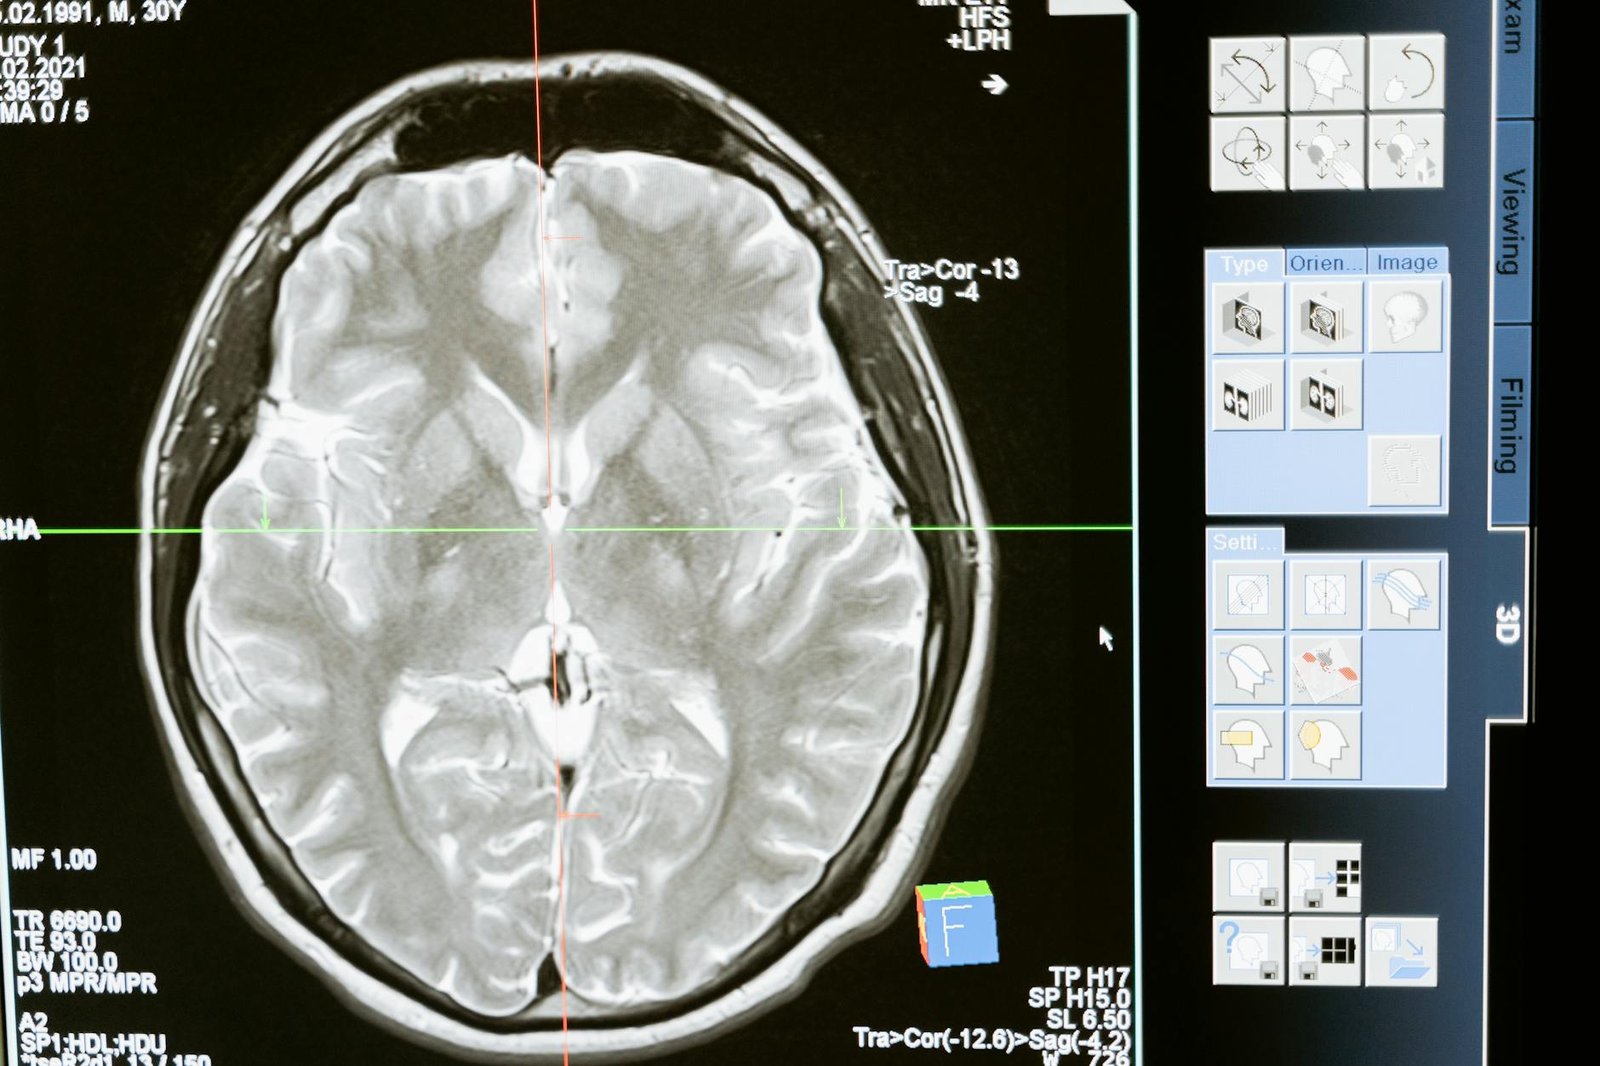

There are 80,000 people living with a brain tumor in England alone, with a patient receiving a diagnosis every two hours. Brain tumors kill more children and adults under the age of 40 than any other cancer, and incidences and deaths from brain tumors are on the rise.

With only 12% of brain tumor patients surviving beyond five years of their diagnosis, it is crucial for these patients to be as robustly and accurately informed as possible in their search for treatment options – especially when it comes to clinical trials, as it is often difficult to find and understand relevant information about them.